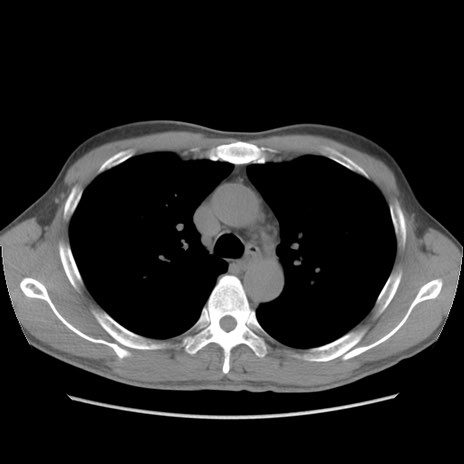

症例56 CT(横断像)